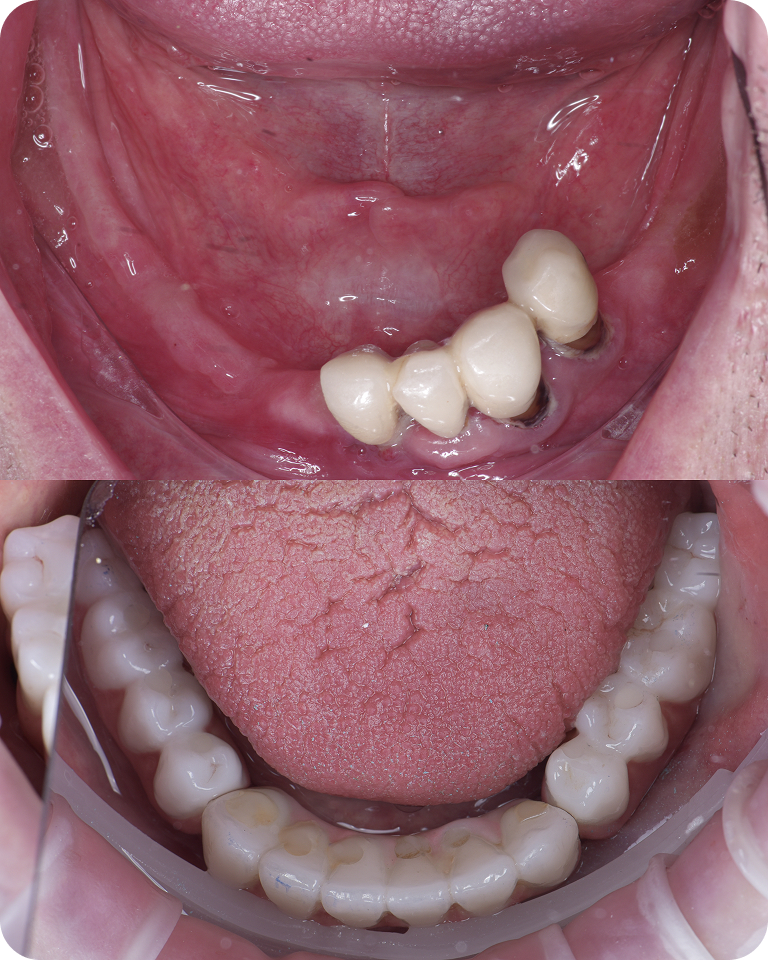

Улыбка до/после

Несъемные протезы

Открытое небо

Даже при сильной атрофии